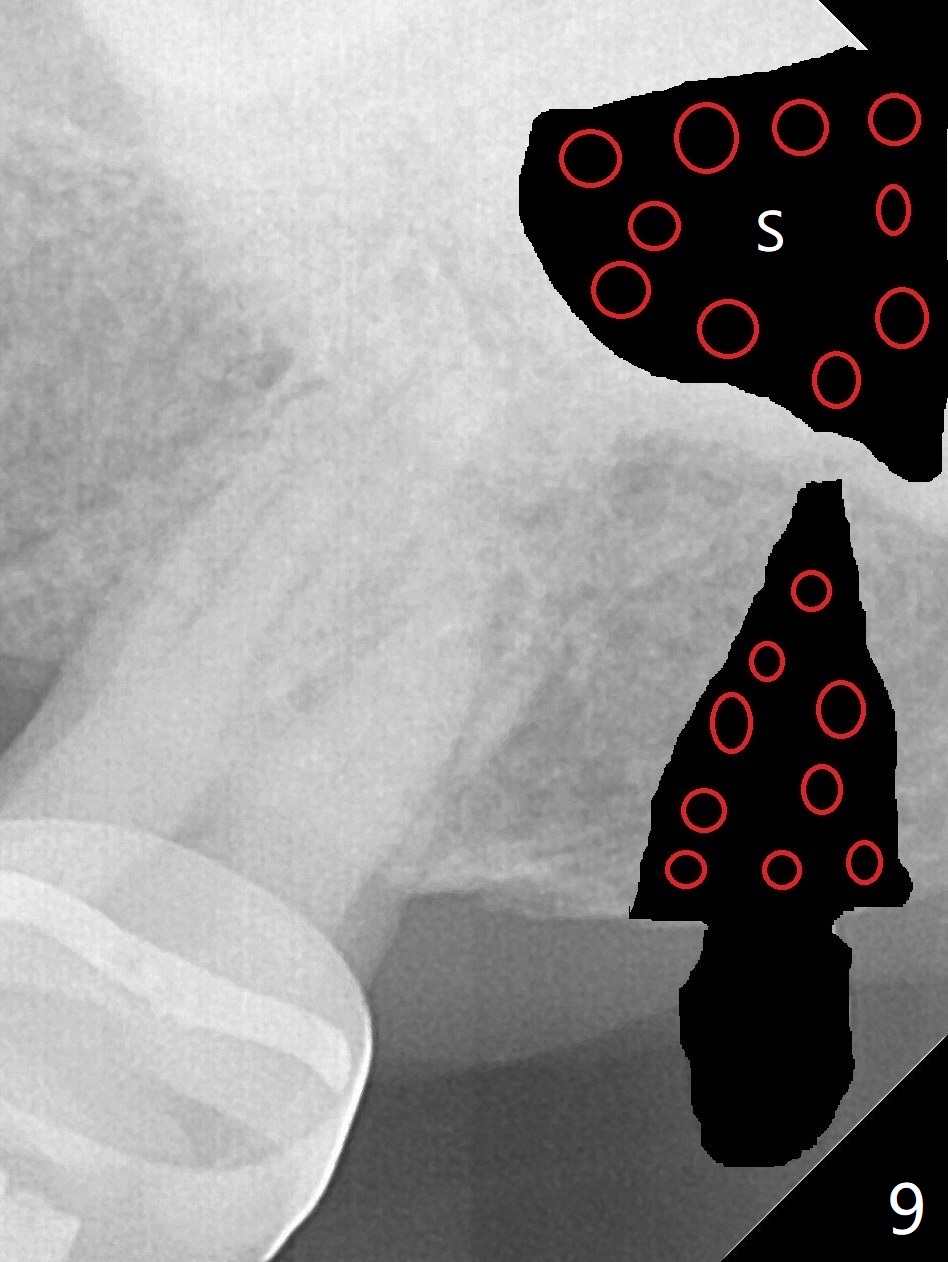

为了在左上6,左下7种植,使用右上3至左上5作为支抗推左上7远中,但是六个月效果不显著(图一),CT显示阻生牙(图一,二:8)没有阻挡。7远中植入1.6x8毫米微型植体,不过接近7根尖(图三),微型植体应该改变角度,而且往远中颊侧移位。最后效果不错(图四),植体马上启用(图五),而且同时取模做左下7导板。在微型植体牵引下,左上7的确往远中移位(图六,与图四对比),但是植体松动,马上植入3x10(2)毫米一段式植体,由于8阻挡,后者没有完全就位,稳定性差,没有启动。几天后也脱落。病人急着完成治疗,因为咀嚼困难。补救方法便是拔除阻生牙9(图七:x),让植体完全就位。切开后发现牙槽嵴处严重骨质吸收缺损(图八:D),离7很近,不适合种植。拔除8后(图九:S(socket)),两处植骨(粘性,图十),覆盖PRF膜,缝合。矫正九个月6空间相当双尖牙(图十二),还想增加2毫米才种植,病人急于完成治疗,所以再次植入微型植体,不同之处是切开,发现7远中颊侧骨质密度低(用探针),因此微型植体在腭侧植入(图十一:P),扭力似乎高,1.6x8毫米植体仿佛植入8牙槽窝(图十二:红虚线)。微型植体牵引一个月,磨牙缺牙间隙大约前磨牙大小,准备在远中(图十三)植入直径小植体(图十四),当后者整合时,用它继续推7。